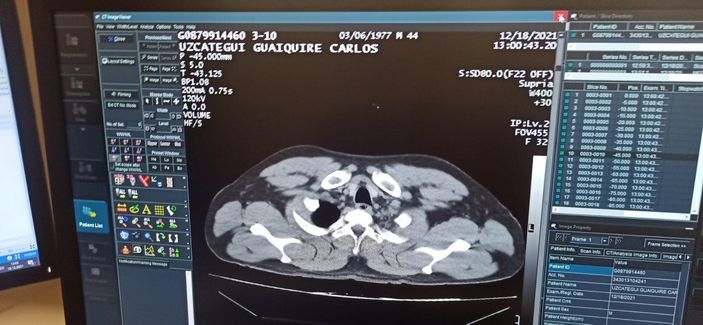

Durumundan şüphelenilen yolcu, yapılan mülakatta 12 kapsül şeklinde sarılı kokain yuttuğunu beyan etti.

Tomografi kontrolünde de mide ve bağırsaklarda tespit edilen kapsüllerin ameliyatla alındığı şüpheli, taburcu olmasının ardından adliyeye sevk edildi.